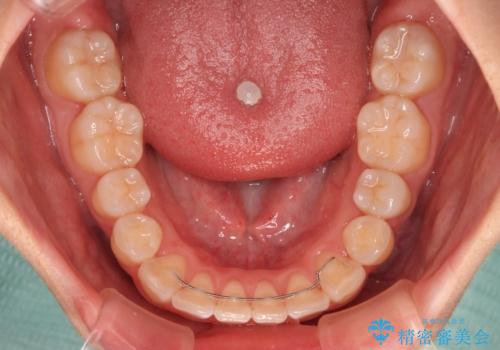

【モニター】八重歯を片側の抜歯矯正で治す メタルブラケット装置

- 八重歯とずれた正中を気にして来院された患者様です。

お仕事の予定を調整しやすく、平日の昼の時間帯に通院可能であったので、非常にスムーズに治療を進めることができ、1年半で無事に治療を終えることができました。